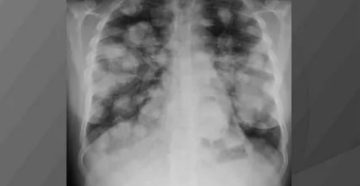

Секундарное поражение легких Метастазы в легких можно диагностировать, используя рентген При постановке диагноза метастаза в…